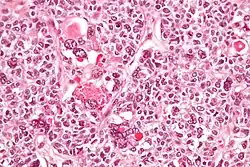

| Micrograph of a juvenile granulosa cell tumour with hyaline globules. H&E stain. | |

Juvenile granulosa cell tumors can be distinguished from adult granulosa cell tumors on histology by their abundant, eosinophilic cytoplasm; primitive, highly mitotic nuclei in polygonal cells; and disorganized follicles.[12][13]